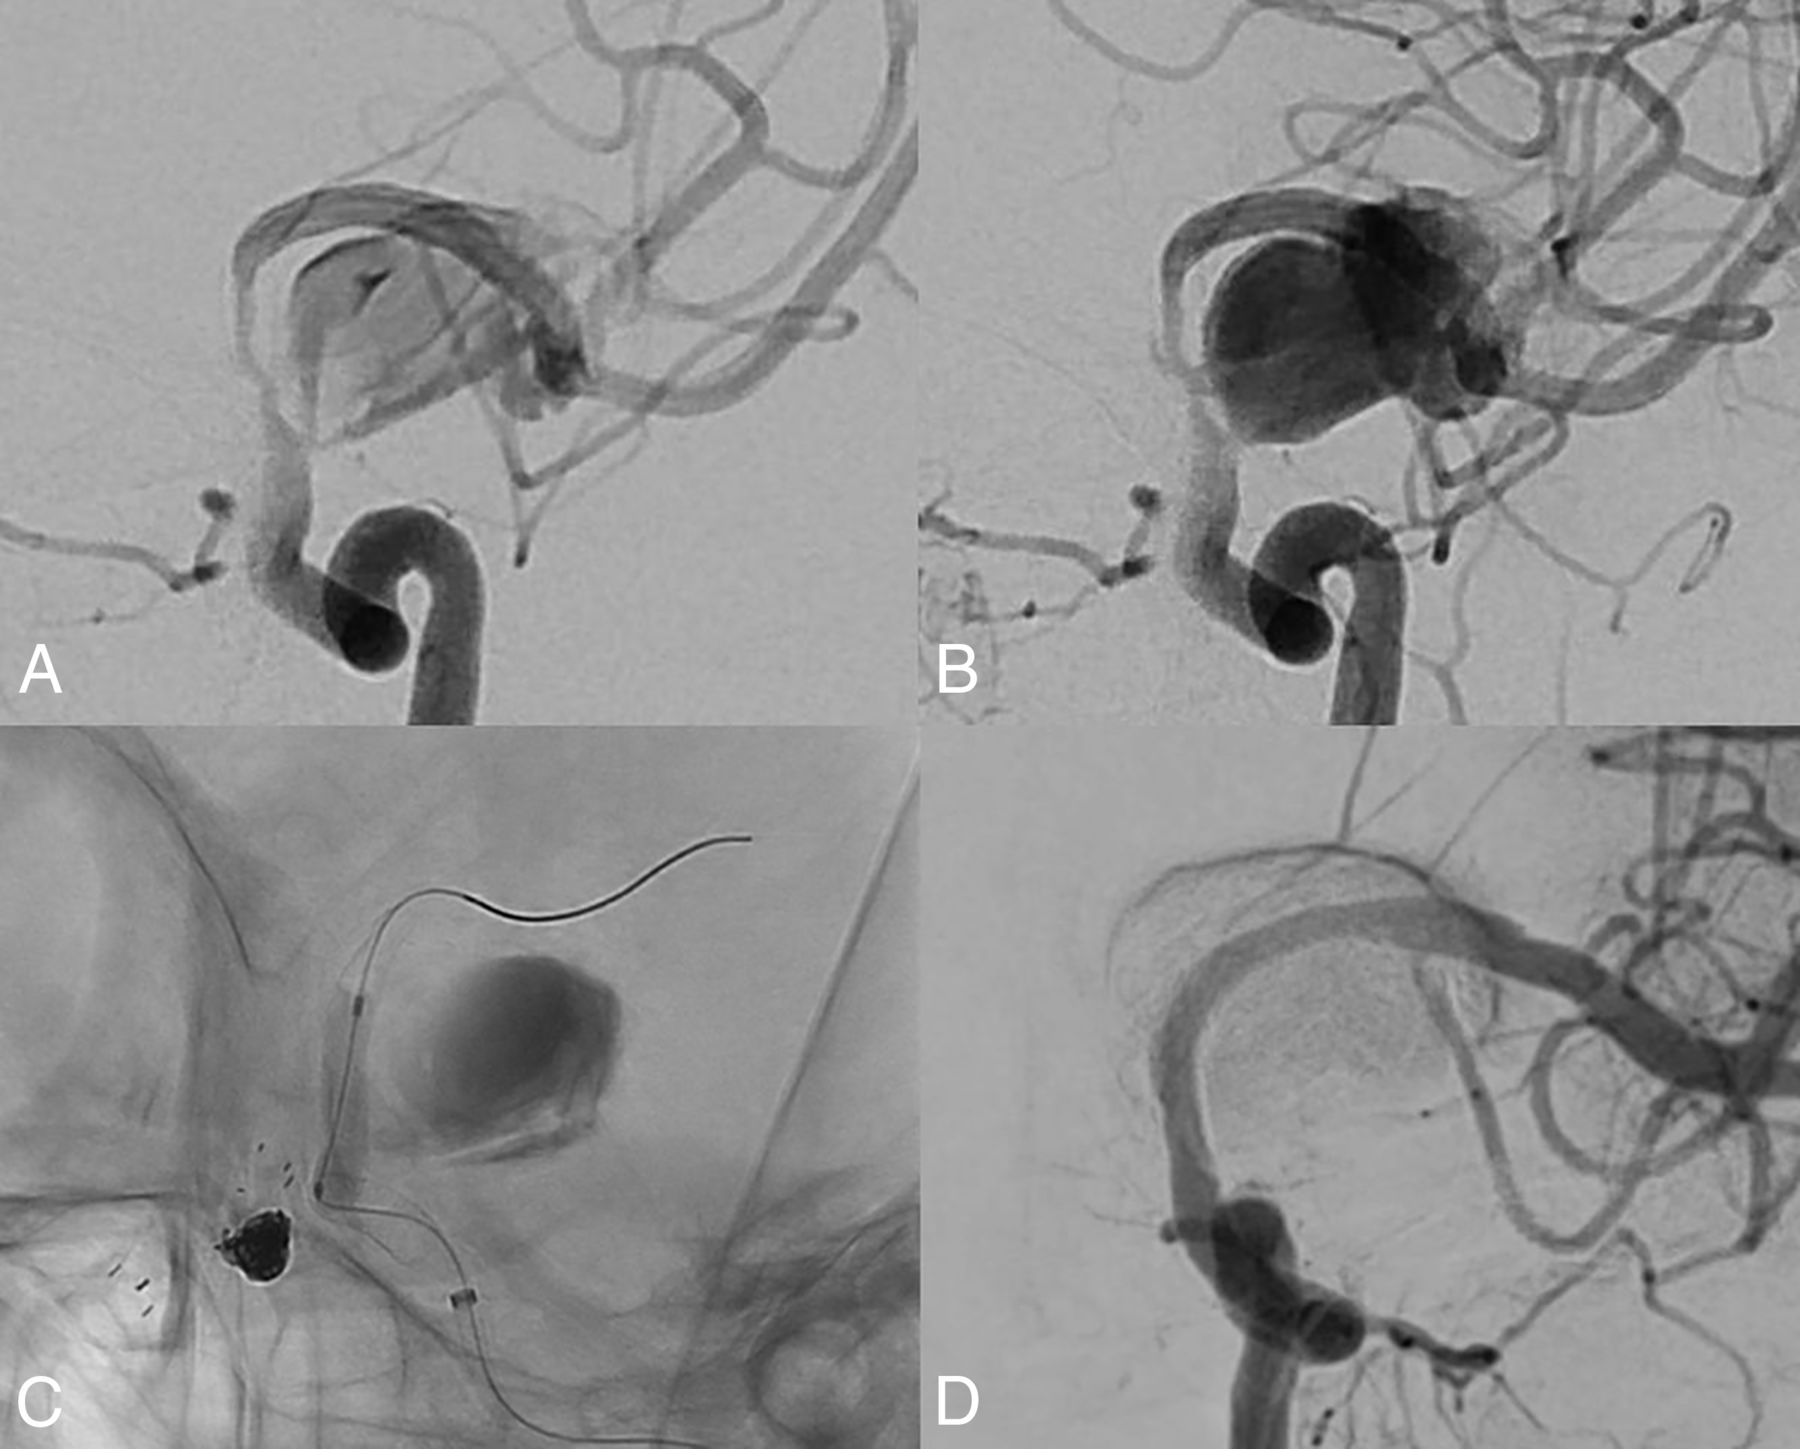

In-stent balloon angioplasty is performed when the stent-to-wall apposition is poor or stenosis is evident in the parent artery because either condition greatly increases the risk of thromboembolic events and subsequent parent artery occlusion.18,28,29 In addition, high-velocity blood flow into the aneurysm caused by stenosis of the proximal parent artery compromises the effect of FD and might induce delayed aneurysm rupture (Fig 3).20,30,31 However, we found that patients who underwent in-stent balloon angioplasty are more likely to be in the no-effect group (OR = 0.05, P = .004). Of the no-effect group, 6/17 (35.3%) patients underwent in-stent balloon angioplasty, while 3/34 (8.8%) in the effect group underwent angioplasty. To the best of our knowledge, no other study has shown that balloon angioplasty compromises the effect of FD. Because FD efficacy is greatly affected by pore density, interventionists sought to maximize this density using the push-and-pull technique at the unconstrained area of the parent artery during FDs deployment. This balloon angioplasty might increase the pore density in the non-neck area and decrease it in the neck area. However, stenosis of the parent artery confounds the effects of balloon angioplasty on the FDs. As mentioned above, angioplasty was performed when stenosis was apparent. Such stenosis of the parent artery is more likely to occur owing to the mass effect than the size of the aneurysm. However, there was no significant trend toward increased aneurysm size in parent artery stenosis in our study (effect group, 21.9 mm [SD, 8.6 mm] and no-effect group, 25.9 mm [5.4 mm], P = .151). In addition, this information should be interpreted with caution, given the low incidence of balloon angioplasty. Many studies have found that balloon angioplasty is required during FD. Our findings imply that excessive balloon angioplasty, which is performed along the whole stent or when there is a slight suspicion of poor stent-to-wall apposition, should be avoided.

High-velocity blood flow into the aneurysm was caused by proximal parent artery stenosis after flow diversion. Early artery phase (A) and late artery phase (B). The high-velocity blood flow disappears immediately (D) after balloon angioplasty in the stent (C).